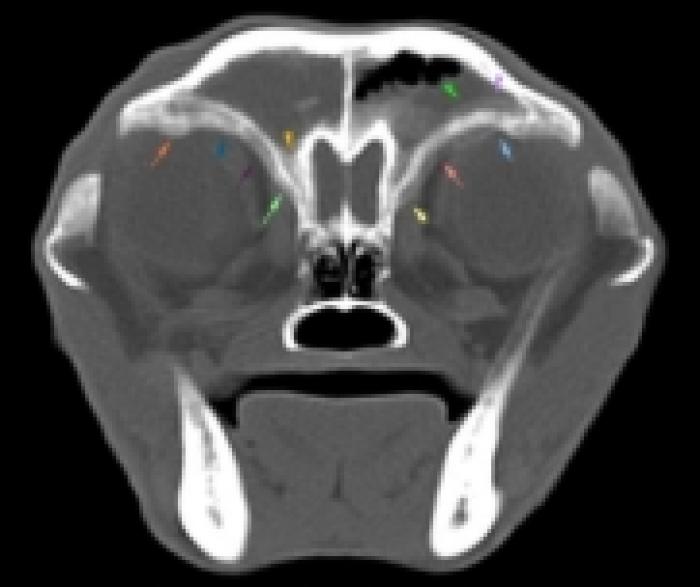

Estudio radiológico de cabeza (laterolateral derecha, ventrodorsal) y senos frontales (cráneo-caudal en flexión cervical): imagen compatible con fístula oronasal en área de pieza 204. En este momento no se aprecian alteraciones en los senos (Figura 4).